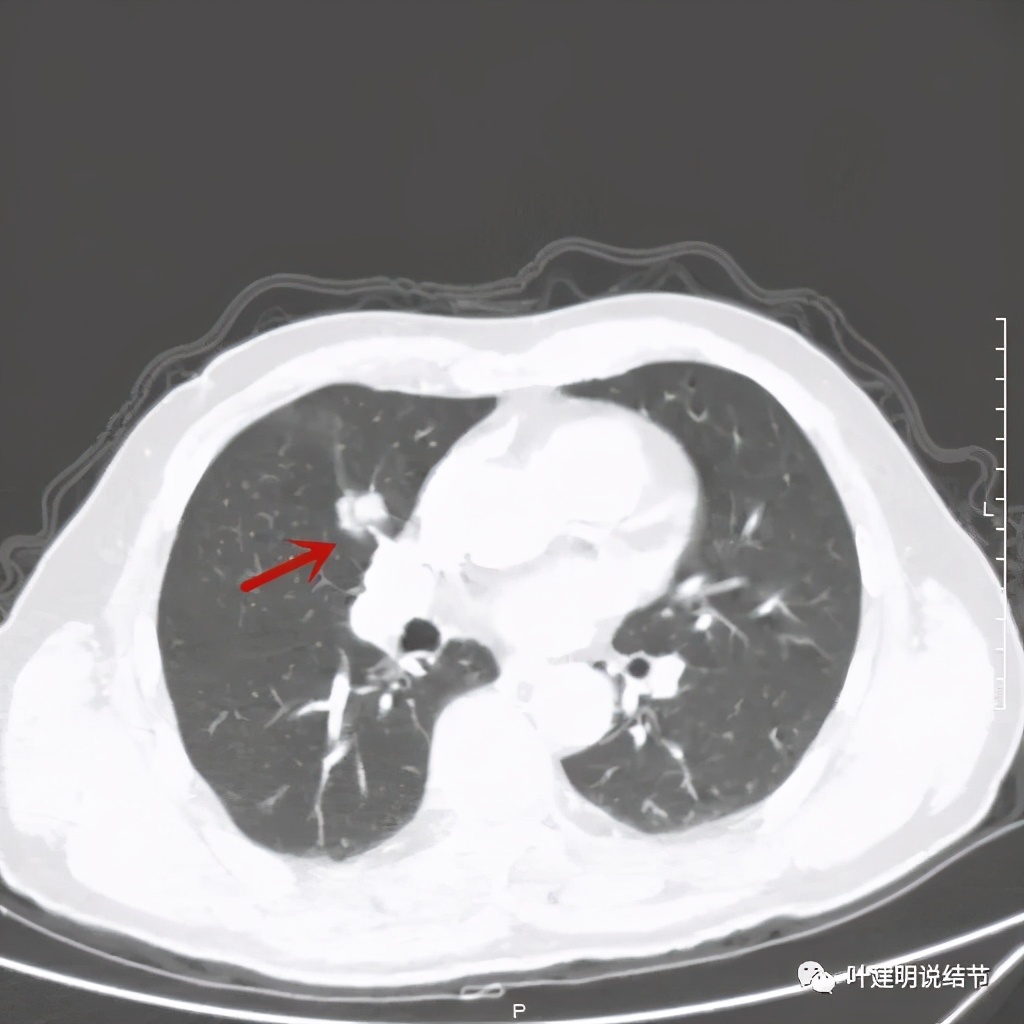

那么当时的胸部影像又是如何的呢?

病灶有分叶及胸膜牵拉

以上几图示病灶膨胀感明显,无卫星灶,周围无渗出性改变